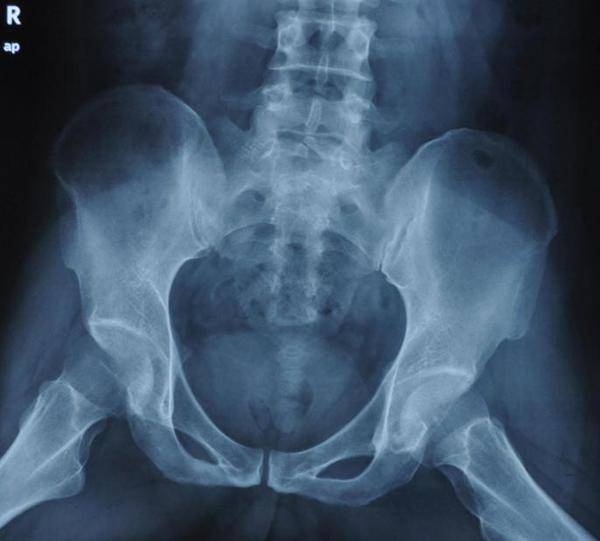

这名患者3年前开始感到两侧髋骨疼痛,当时他以为只是劳累所致,因此并未及时就医。然而,去年9月,疼痛愈发严重,已经严重影响到了他的日常生活,甚至连上下楼梯和下蹲这样的基本动作都变得异常吃力。到医院拍片做检查,确诊为股骨头坏死4期。这是股骨头坏死最严重的阶段。对患者本人来说,也是个“致命”的打击。

另外,张主任也强调,股骨头坏死的治疗并非一蹴而就,每个患者的具体情况都有所不同,因此在治疗过程中需要根据患者的具体情况制定个性化的治疗方案。同时,她也提醒广大患者,股骨头坏死发病隐秘,当前大众对这种疾病的认识仍然不足,通过常规的X光检查也很难对早期病症进行判断,核磁共振依然是最好的早期检查方式。如果抬腿屈膝或下蹲时出现髋部疼痛的情况,一定要引起重视,及早排查,及早治疗!